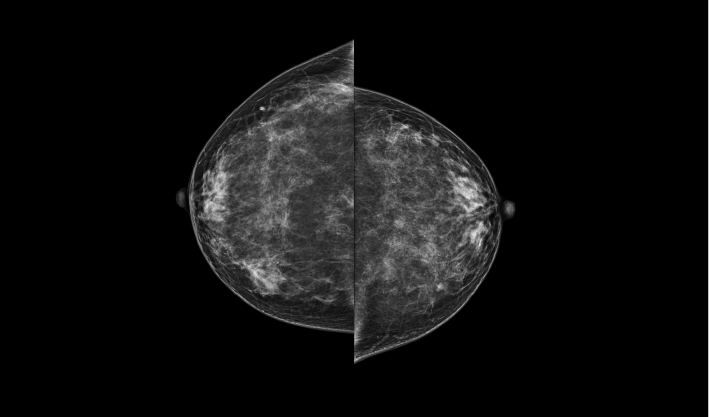

头尾位(CC位) 内外斜位(MLO位) 补充体位(根据需求)

一键式视图切换

致力于致密乳腺的早期癌变筛查和微钙化簇精准定性。